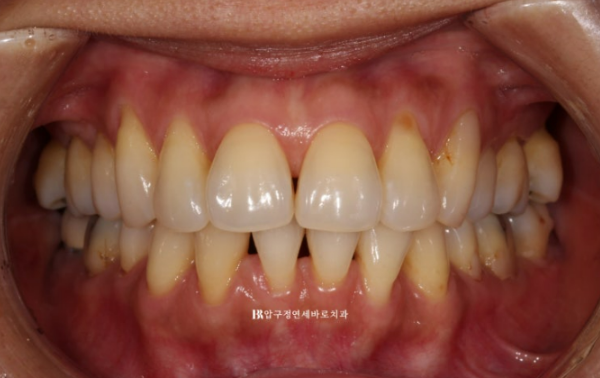

23.04~23.08

비스듬한 측면에서 봤을 때에도 블랙트라이앵글이 많이 줄어든 것이 보입니다.

치간삭제와 고무줄을 병행하면서 튀어나와있었던 앞니를 뒤로 꽤 많이 넣었습니다.